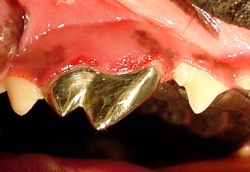

Los problemas que aquejan los tejidos periodontales son varios aunque su etiología primaria siempre es la misma, el alimento y las bacterias que se pegan a los dientes formando la placa dento bacteriana (PDB) y el sarro que destruyen lentamente pero de manera progresiva los tejidos de sostén dental. La enfermedad periodontal es la enfermedad de mayor incidencia y prevalencia en perros y gatos por lo que su diagnóstico, prevención y tratamiento es uno de los retos que el médico veterinario tiene en su trabajo clínico. La enfermedad periodontal es la causa más común de enfermedades como endocarditis bacteriana y artritis infecciosa por lo que el propietario y médico tratante deben de tener especial interés en la prevención y tratamiento de esta patología. La enfermedad periodontal se clasifica dependiendo de los tejidos afectados así como según el grado de destrucción del tejido óseo. Según el tejido afectado como “Gingivitis” cuando afecta la encía libre y papilar, y “Periodontitis” cuando ya afecta el tejido óseo y el ligamento periodontal formando destrucciones del hueso alveolar muy características de la enfermedad denominadas bolsas periodontales las cuales según la forma de destrucción pueden clasificarse como horizontales o verticales. La periodontitis se diagnóstica con una sonda periodontal que es un instrumento que tiene líneas de medición en su punta de trabajo y que se introduce en el surco gingival para medir en milímetros la destrucción ósea alveolar. Otro método de diagnóstico es la radiografía periapical en la cual se puede observar claramente el grado y forma de destrucción ósea alveolar.